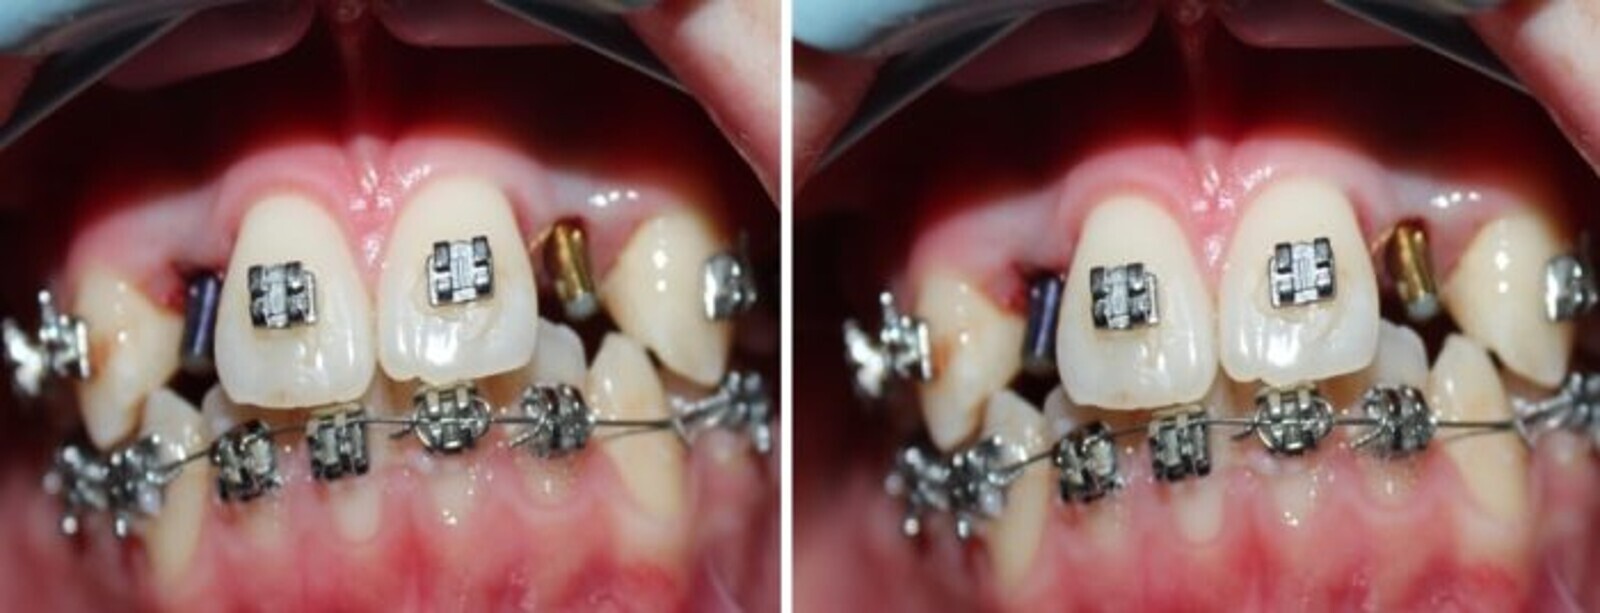

Luego de la extirpación quirúrgica de la pieza y del proceso quístico se procedió a realizar un tratamiento de ortodoncia convencional para alinear, nivelar y preparar el terreno para la rehabilitación implanto protésica.

Fig. 5. Implante rectos NTI colocados sin realizar incisión ni sutura.